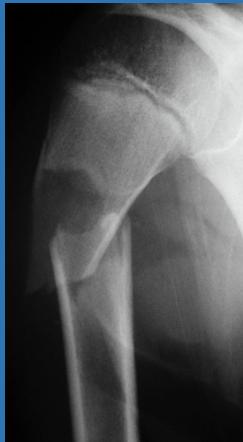

Case 3: Pathological Fracture (11 years old)

Clinical Presentation

- Pain in right arm after fall at home

- No significant medical history

- Incidental discovery of bone lesion on X-ray

Diagnosis: Simple Bone Cyst

Characteristics

- Solitary (unicameral) lesion

- Children (typically 5-15 years)

- Metaphyseal location

- Not seen in adults

- Commonly discovered by pathological fracture

Treatment Options

- Observation: Cyst might heal spontaneously

- Multiple bone marrow injections

- Fracture fixation: Flexible intramedullary nailing

- Surgical curettage and bone grafting